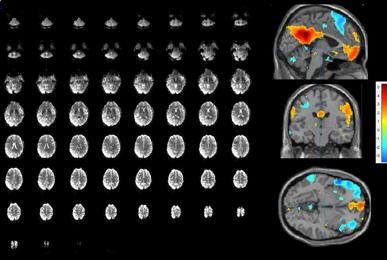

7 Tesla Neuroimaging Studies with the Tic-Tac-Toe Radiofrequency Coil System

Recently FDA-approved 7 Tesla (T) MRI can provide improved signal-to-noise ratio, resolution, and image contrast when compared with standard clinical MRI scanners (usually 1.5T or 3T). However, proton imaging at higher frequencies (~300MHz) and shorter wavelength (~13cm in brain tissues) can lead to inhomogeneities in the images and potentially cause high localized radiofrequency (RF) power deposition in the tissue. The Tic-Tac-Toe (TTT) RF coil system provides improved homogeneity and reduced power deposition. It is achieved thanks to an innovative coil design and a methodology of operation. Several clinical MRI sequences have been performed and compared with commercial RF coils, demonstrating the superior performance of the Tic-Tac-Toe RF coil system. Numerous clinical studies including NIH funded studies (~2,000 subjects) are currently being conducted using this coil at the University of Pittsburgh.

b) a) c) The Tic-Tac-Toe (TTT) radiofrequency head coil for 7T MRI Fig 1: in a), the implemented 16-channel TTT transmit RF coil; in b), the computational RF coil in c), the implemented RF coil with an 32-channel receive insert Fig. 2: The B1+ (magnetic field responsible for spin excitation) field homogeneity is highly degraded at 7T MRI due to a higher operational frequency (~297MHz). The TTT presents a more homogeneous field distribution when compared with the NOVA coil (a commercial coil) [1]. Measured Tic-Tac-Toe Measured Nova coil Regions with low B Simulated Tic-Tac-Toe B + maps in the brain: TTT vs NOVA RF coils TTT coil NOVA coil TTT coil NOVA coil Image comparison with the 32-channel NOVA commercial RF coil a) b) Fig. 3: In a), Turbo spin echo (TSE) sequence using the TTT coil with resolution of 0.4x0.4x2mm. In b), the same TSE sequence acquired with the commercial NOVA coil. In c), FLAIR sequence acquired with TTT coil with resolution of 0.7x0.7x2mm. In d), the same FLAIR sequence acquired with NOVA coil. The arrows point to regions of dark spots in the NOVA coil images and compare with similar regions on the TTT coil images [1]. c) d) High-resolution susceptibility weighted images showing cortical microvessels Fig 4 SWI images acquired at 0 2x0 2x1 5mm resolution In a) an axial slice of the whole brain image acquisition In b) and c), zoomed versions of a), detailing the micro-structures a) b) c) High resolution angiography without contrast agents 380μm a) b) Fig 5: Maximum intensity projection orientation and small vessels detectability isotropic image showing whole brain isotropic acquisition In d), 0 20mm are only detectable at higher resolution

Finger tapping task: activation of Functional MRI a) Diffusion MRI and fiber tracking Post-mortem a) a) b) Fig 7 In a), an structural MPRAGE image acquired at 0 75mm isotropic (skull removed using FSL package) In b), fiber tracking based on DTI acquisition, 64 directions, 1 5mm isotropic resolution The colors are defined for different orientations of the fibers Fig 8: In a), susceptibility weighted images acquired at 0 35mm isotropic, 32 min acquisition time, in a post-mortem brain fixated with formalin In b), a photograph of similar slice in the same brain Table 1: 7T MRI studies conducted at the RF Research Facility at University of Pittsburgh White matter legions (circle): Multiple Sclerosis study Stroke (circle): sickle cell disease study Automatic hippocampus segmentation: Midlife Neurocognitive Lacunar infarct (arrow): depression study White matter hyperintensities (arrows): Healthy Brain aging study (left) and Small Vessels disease in preclinical Alzheimer’s disease study (right) Fig 9: Sample of some studies listed in Table 1 using the developed 16 array (Fig a) There are 4 completed studies and 13 ongoing patient studies with approximated 2 000 patients scheduled FUTURE DIRECTIONS 64-channel Tic-Tac-Toe RF transmit coil for 7T MRI 0 Fig 10: In a), the 64-channel transmit coil computational modeling [2] To improve the field of view of the projector/monitor in fMRI studies, the frontal panels can be removed, resulting in a 56-channel coil In b), one assembled side of the coil In c), simulated B1+ field distribution: for an 8kW power amplifier capabilities (default in older 7T MRI scanners) a homogeneity (measured by the coefficient of variationCV) of 15 2% is achieved in the brain For an 16 kW power amplifier (available for the recently FDA approved Siemens 7T MAGNETOM Terra), an CV of 10 6% can be achieved in the brain 16 kW power amplifier: 8 kW power amplifier: a) b) c) max